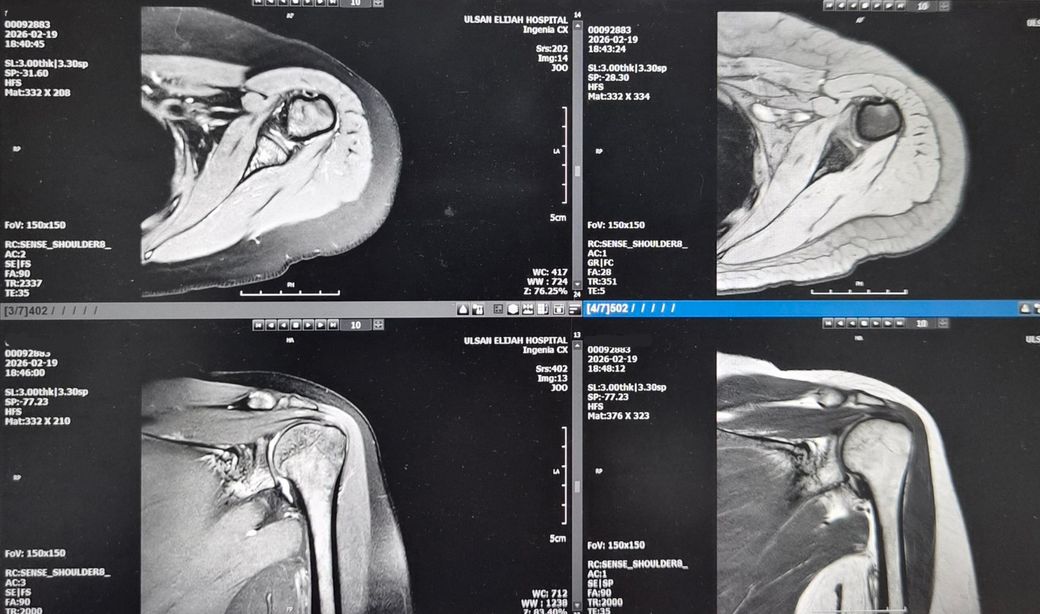

왼쪽어께가 아파서 엑스레이 찍고 MRI저녁에

찍었어요.MRI판독좀 해주세요! 의사소견으로는

골절됬다가 뼈가 붙었다고 했어요. 뼈도좀 튀어나왔죠?그리고

어께충돌증후군이 있다고 치료확인서에 적혀주셨어요. 어께안쪽이 찌릿하고 뭔가 사이에

걸리는 느낌도나요!딱딱 소리도 나구요.

MRI상 "어깨충돌증후군(견봉하 충돌) + 회전근개 자극/염증"이 있어 팔 들 때 걸림·찌릿함·딱딱 소리가 설명됩니다.

과거 골절부위가 붙으면서 살짝 튀어나온 뼈와 건봉 사이공간이 좁아져 힘줄이 마찰되는 충돌 증후군때문에 걸리는 느낌이 납니다. 4개월 전과 비교해봤을때 뼈 사이간격의 큰 변화는 없으나 골정치유부위의 변화가 증상에 영향을 줄수 있습니다. 통증을 유발하는 동작은 피하고, 염증완화를 위한 치료와 회전근개 운동을 꾸준이하는것이 중요합니다. 당분간은 어깨 올리는 자세를 피하고, 물거운물건을 드는건 피해주세요. 빠른쾌유를 빕니다!